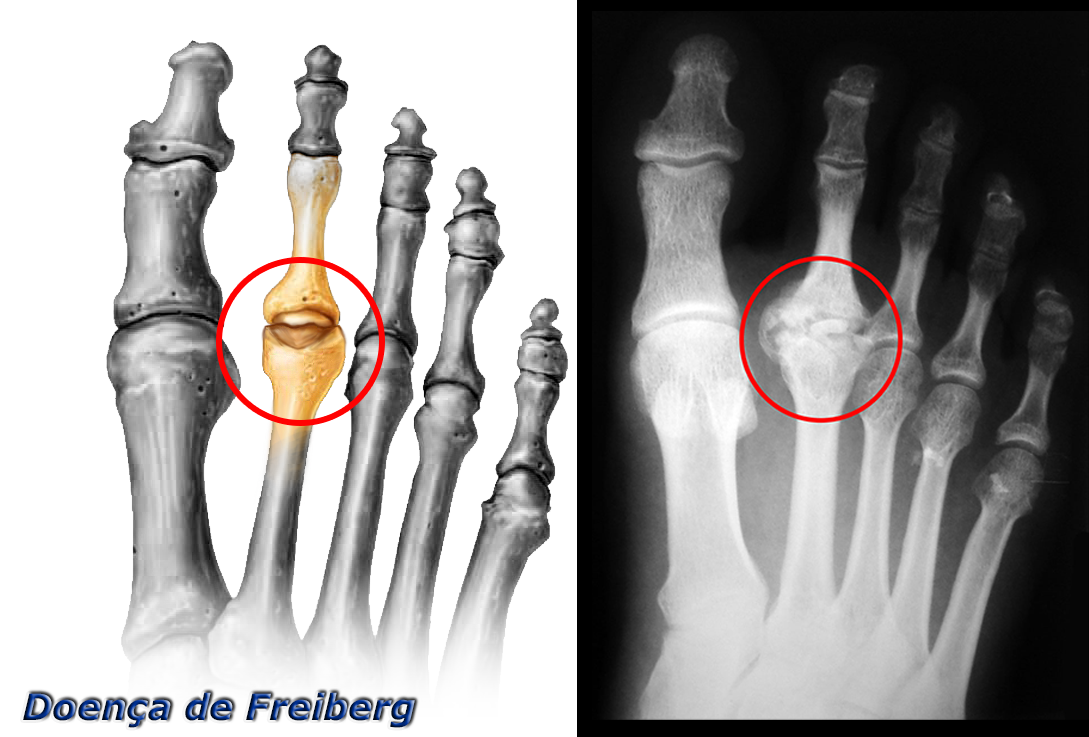

A necrose avascular da cabeça metatarsal, Doença de Freiberg, é uma doença circulatória local que deforma a articulação metatarsofalângica e ocasiona dor e perda do movimento. Mais frequentemente acomete a cabeça do 2º metatarso.